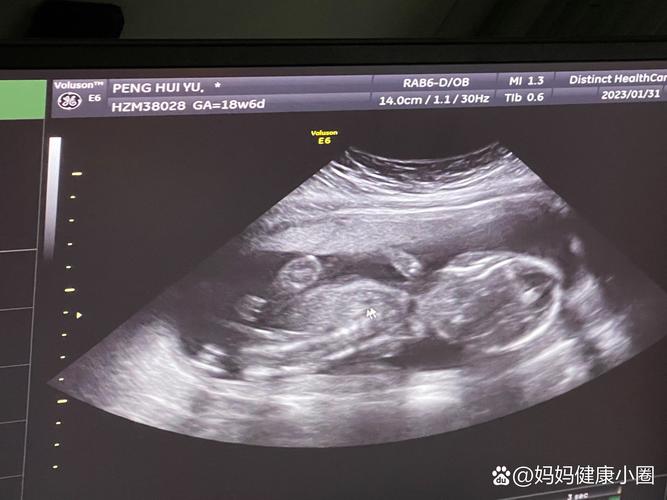

- 生殖器: 如果宝宝姿势合适,通过B超可以清晰地分辨出性别了。